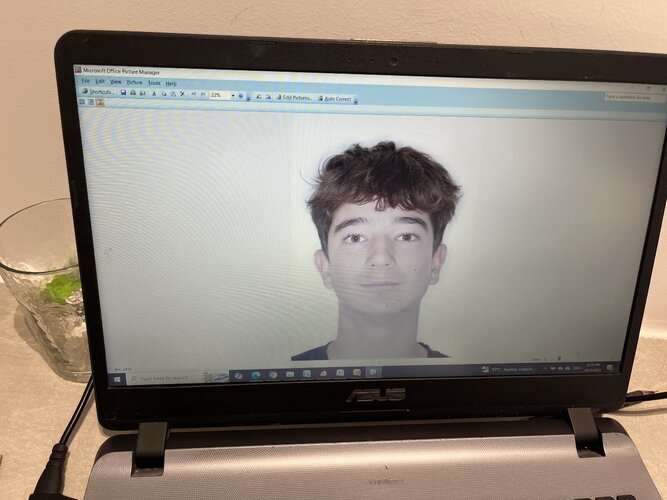

Important to note that my maxilla wasn’t downward grown until braces and headgear I am still 16 and upward thumb pressure is is not really doing anything much (I also had to fix my skeletal issue with my palate because my ortho only did tooth expansion instead of marpe/sarpe (aka breathing issues)